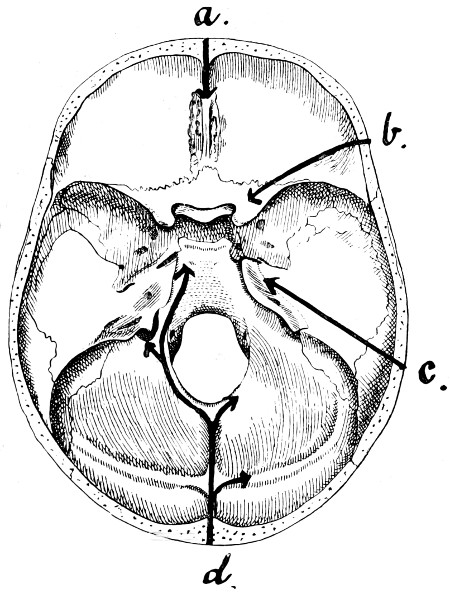

28. Illustrating the lines along which forces received on the vault are transmitted to the base 69

29 A and B. The base of the skull and the base as seen on transillumination 70, 71

30. Plan of the base of the skull 77

31. To illustrate the relation of basic fractures to cranial nerves 81

32-37. The lines pursued by basic fractures 83-8